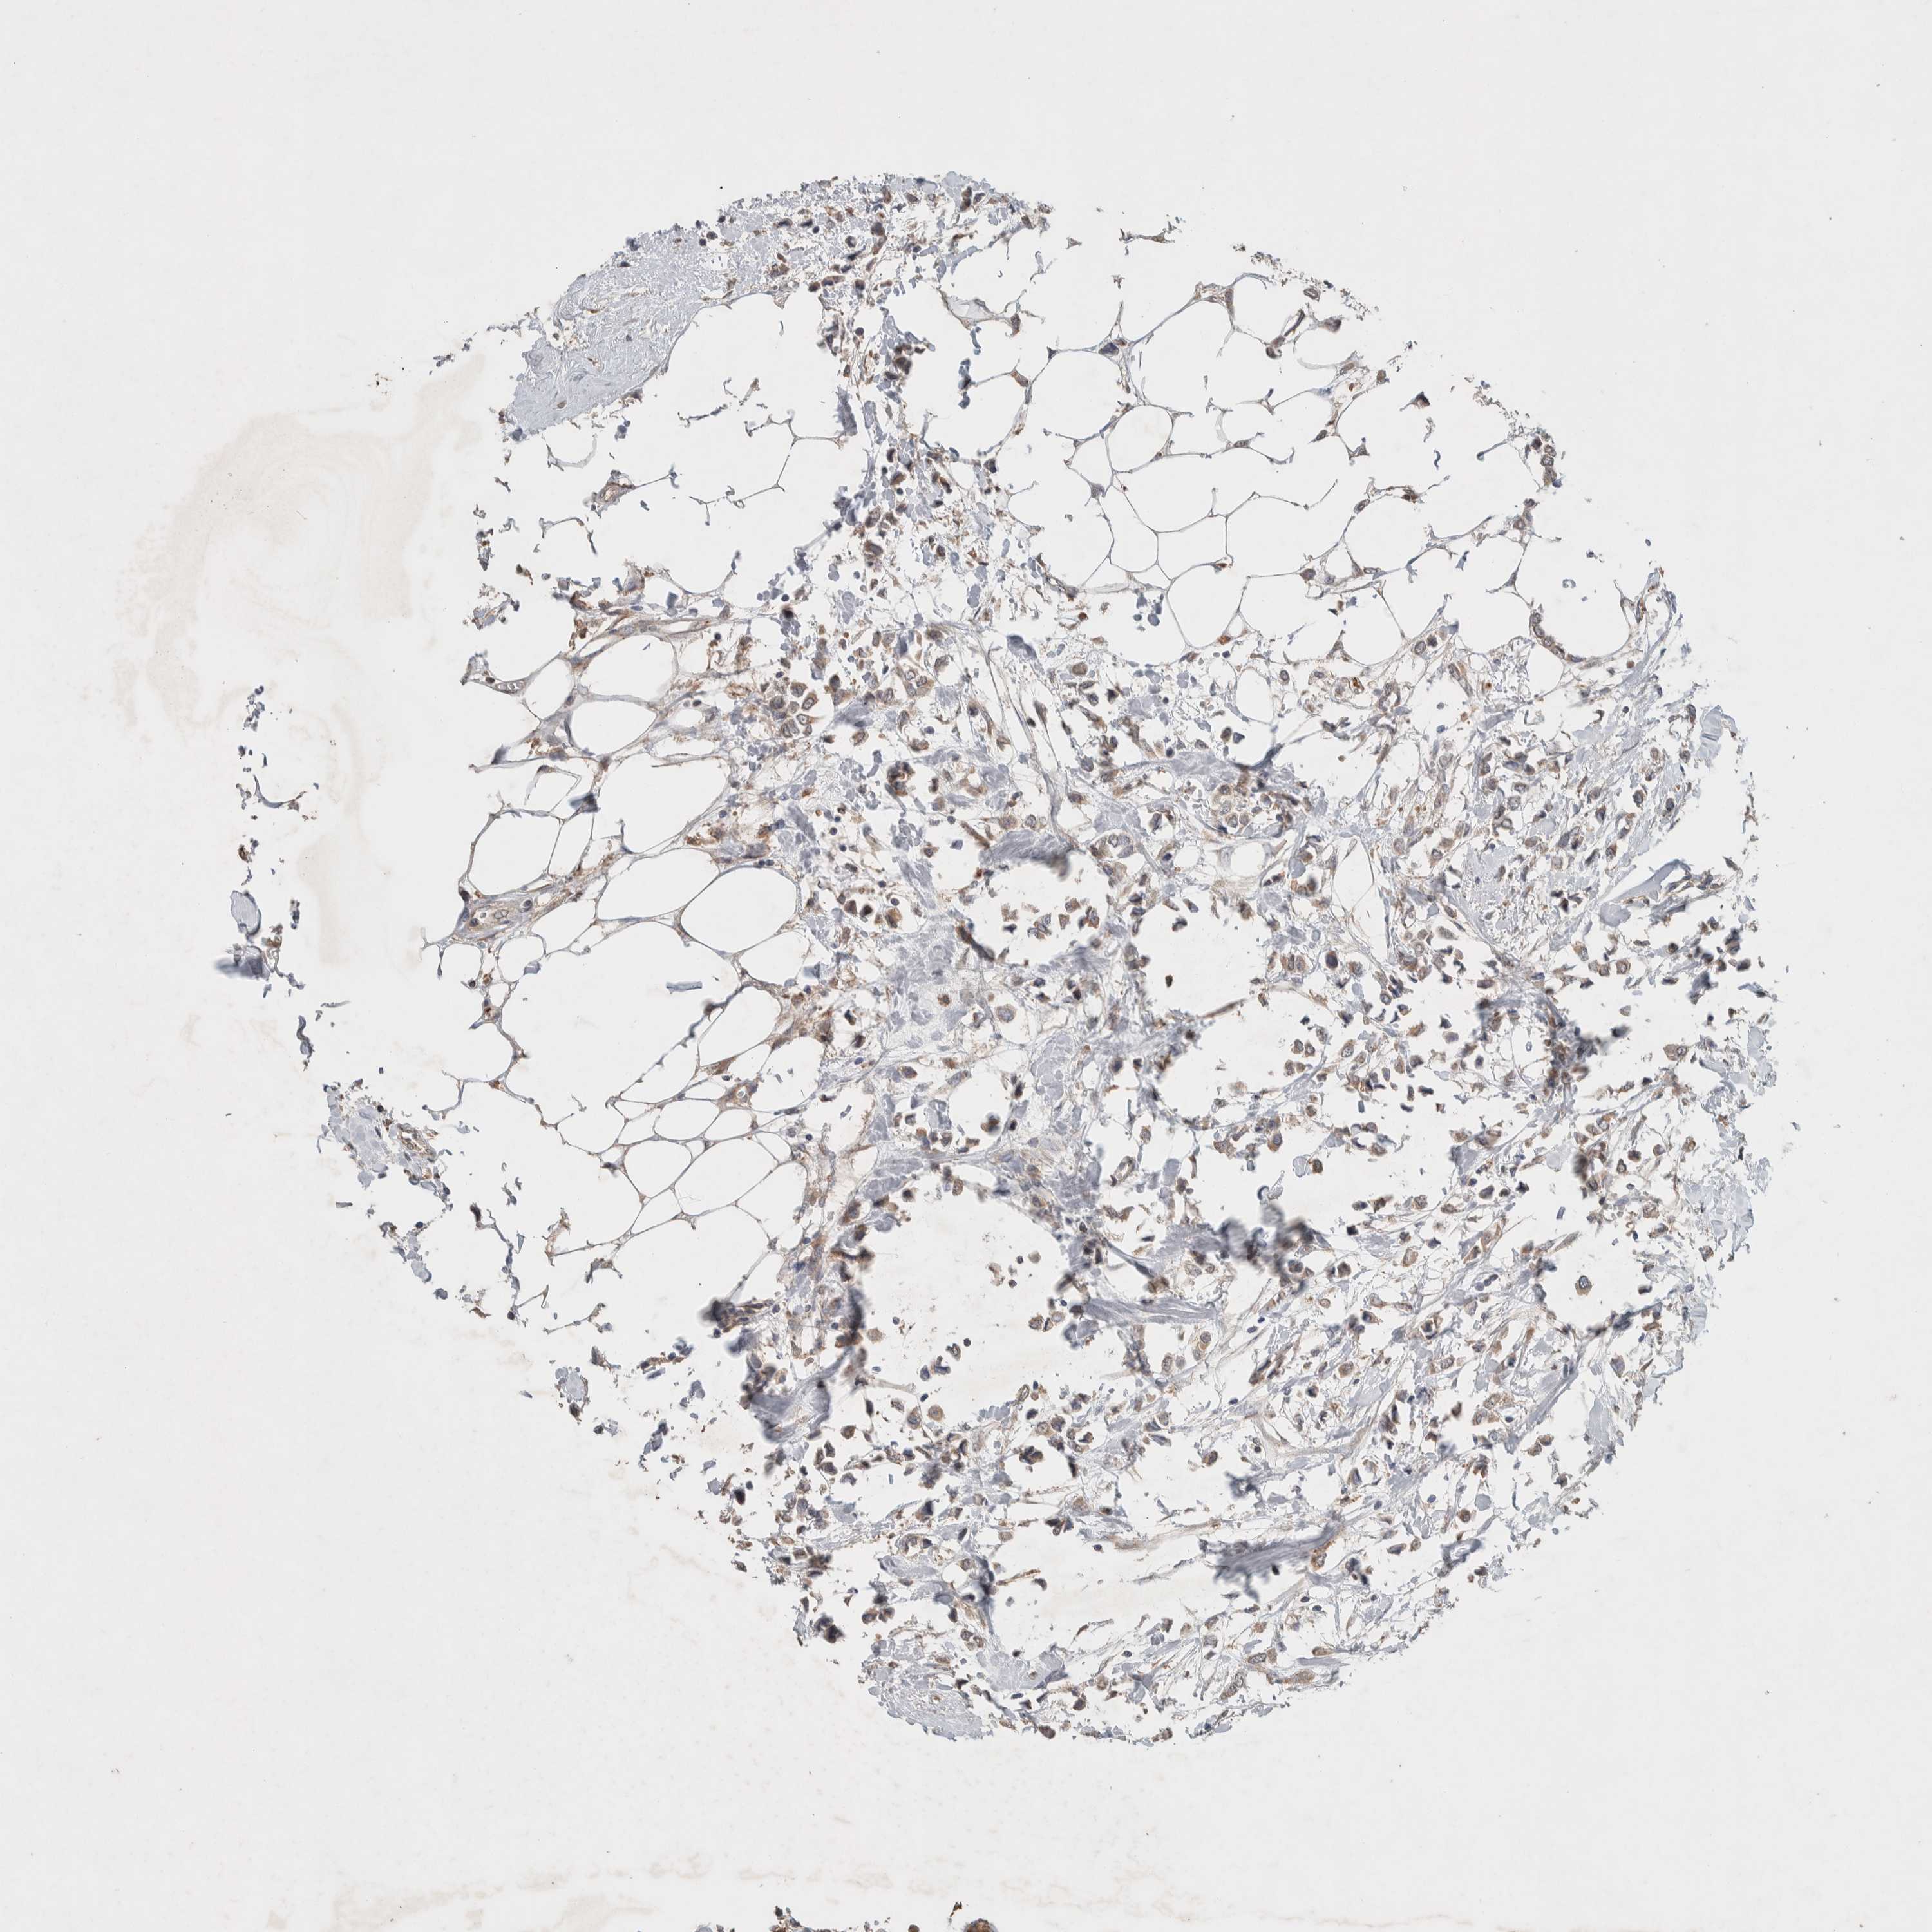

BRCA TCGA BRCA VALIDATION PROTEIN EXPRESSION